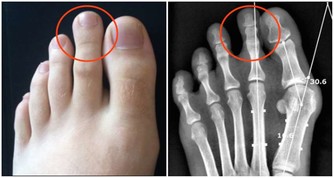

酷愛流行音樂的曉曉只要不是在上班,那耳朵裡一定塞著耳機。尤其在逛街、坐公交車等聲音嘈雜的場合,她都會不自覺地把聲音調高。晚上回到家中看電視時,聲音總是開得很大,自己還渾然不覺。直到有一次媽媽出來問她:「這麼大的聲音,像在電影院一樣,你耳朵吃得消嗎?」。在一次體檢中,經醫生過診斷,她的鼓膜完整、中耳無感染,聽力測試後確診為感音神經性耳聾,聽力衰退程度已經很嚴重。

聽力下降最好一週內就診由噪音環境引起的聽力受損叫感音神經性聽力損害,最好能在一週內就診.